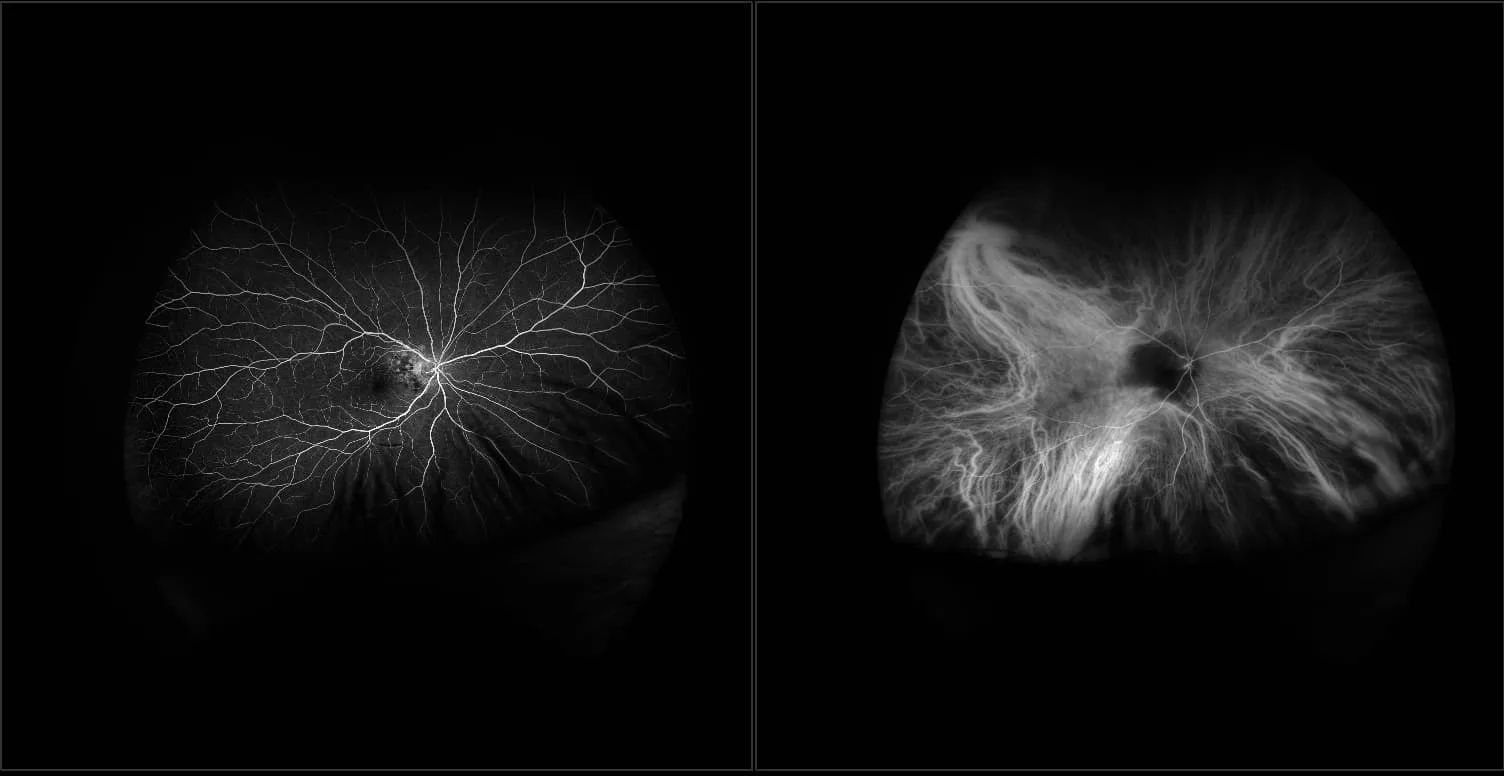

California - Choroidal Melanoma - Montage, RG, RGB, AF

A primary cancer of the eye. It arises from the pigmented cells of the choroid of the eye and is not a tumor that started somewhere else and spread to the eye.